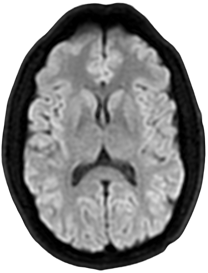

DWI

1.5T

2 x 2 x 5mm

1:02

0.5T

1:35